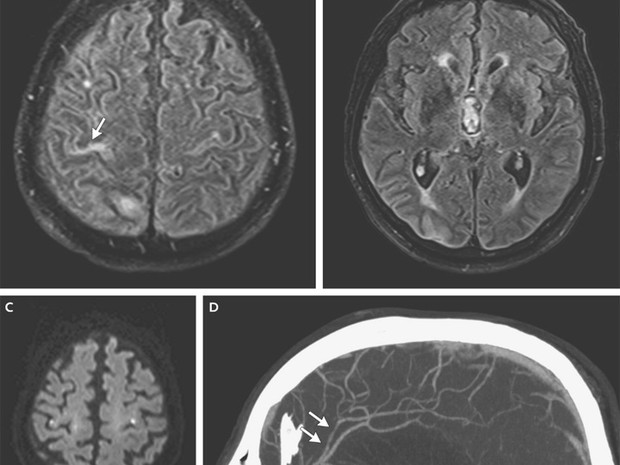

Esta é a conclusão de um grupo de cientistas franceses após a descoberta de que um homem de 81 anos infectado com zika em um cruzeiro no Pacífico Sul, região onde o vírus também circula, desenvolveu meningoencefalite e não se recuperou um mês depois.

"Os médicos devem estar a par de que o vírus do zika pode estar associado com a meningoencefalite", advertem os autores do estudo. Os cientistas descartaram que o paciente de 81 anos tivesse qualquer outro vírus e detectaram zika em seu líquido cefalorraquídeo - encontrado no cérebro e medula espinhal.